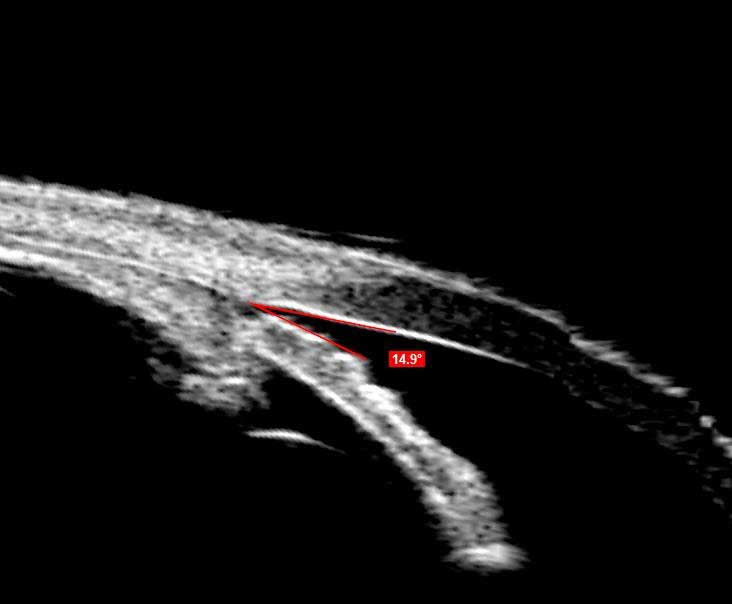

UBM незамінний при візуалізації переднього відрізка ока. Зображення з високою роздільною здатністю UBM дають можливість спостерігати структури, приховані райдужною оболонкою або помутніннями рогівки.

Програмне забезпечення Scanmate надає інструменти для вимірювання кутів, площі та довжини, а також інструмент анотації для позначення патологій. Наповнений водою одноразовий стерильний чохол Clear Scan® Probe є єдиним компонентом, який торкається ока.

UBM зонд застосовується для: Вимірювання ACA; Оцінки рогівки після LASIK; Моніторингу положення ІОЛ; Передопераційної оцінки ICL; Діагностики кіст райдужки та циліарної оболонки; Післяопераційного обстеження глаукоми.